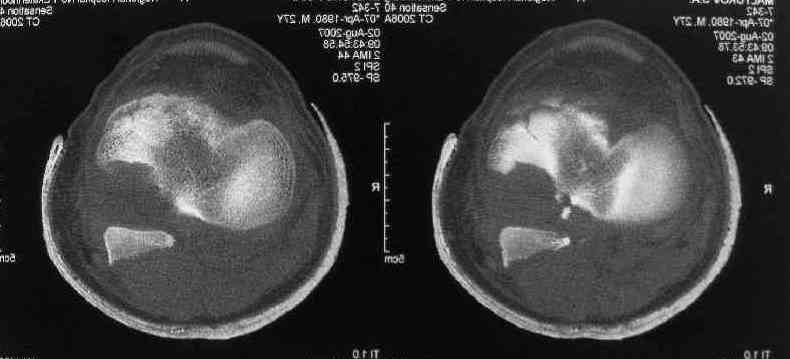

I thank for attaching the CT scan. it makes all the details very clear.

the approach should be standard posterior one (same that we use to fix the avulsed PCL).

the fragment is rotated and hence may require some manipulation, especially in flexion of the knee joint.

fixation may be with cancellous screw and washer.

ONLY IMPORTANT THING IS THAT THE SURGERY MUST BE DONE VERY FAST, it is already 2 weeks old; 10 days more

and it will become very difficult. at present also a good mobilisation of artery and nerve would be

essential before proceeding with reduction otherwise there are good chances of injury to vasculature and

frustration of very difficult reduction.

Для определения доступа сагитальные срезы менее информативны, необходимо иметь корональные срезы.

Корональные срезы дают информацию об апексе перелома, и также информацию о вовлечения суставной поверхности, что является немаловажным для прогноза.